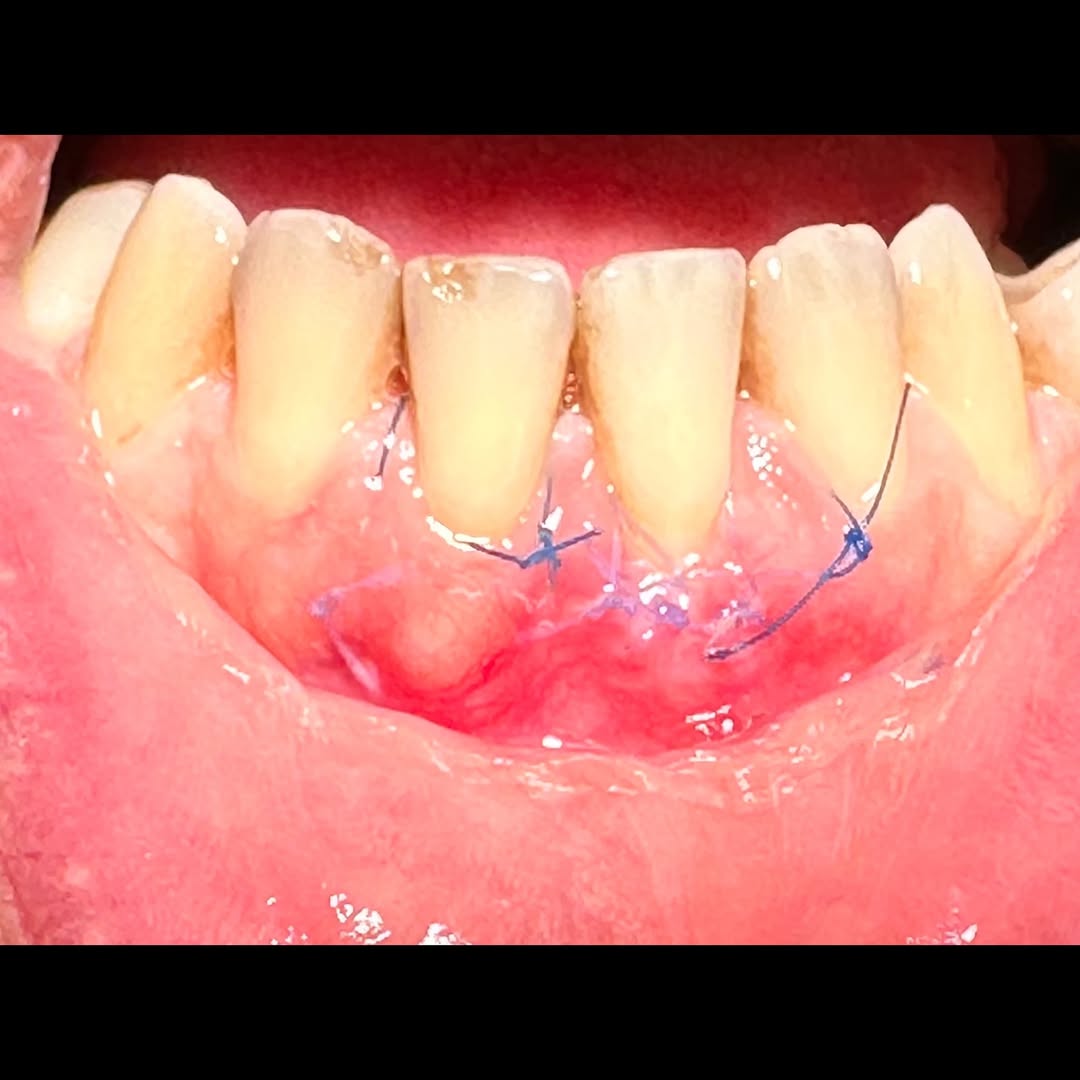

Durante una mañana, asistirás a una Cirugía Mucogingival de recubrimiento radicular de recesiones múltiples en IV y V sextante (36 a 43).

Gracias al uso del microscopio y a la proyección en tiempo real en pantalla, verás exactamente lo mismo que veo yo durante la cirugía, sin tener que estar

Aprende la planificación y técnica de la cirugía Mucogingival para el recubrimiento de recesiones y aumento de banda queratinizada en el sector anteroinferior

Una estancia clínica pensada para quienes quieran iniciarse o dar un paso más en el campo de la cirugía mucogingival. Durante esta experiencia tendrás la oportunidad de aprender en directo cómo se planifica y se lleva a cabo una cirugía mucogingival mediante técnica de Túnel.

La sesión

Formación teórico-práctica completa sobre las técnicas más avanzadas en cirugía mucogingival. Durante dos días intensivos, los participantes aprenderán desde la evidencia científica y la anatomía de las zonas donantes hasta la ejecución de injertos, cubrimiento radicular y aumento de